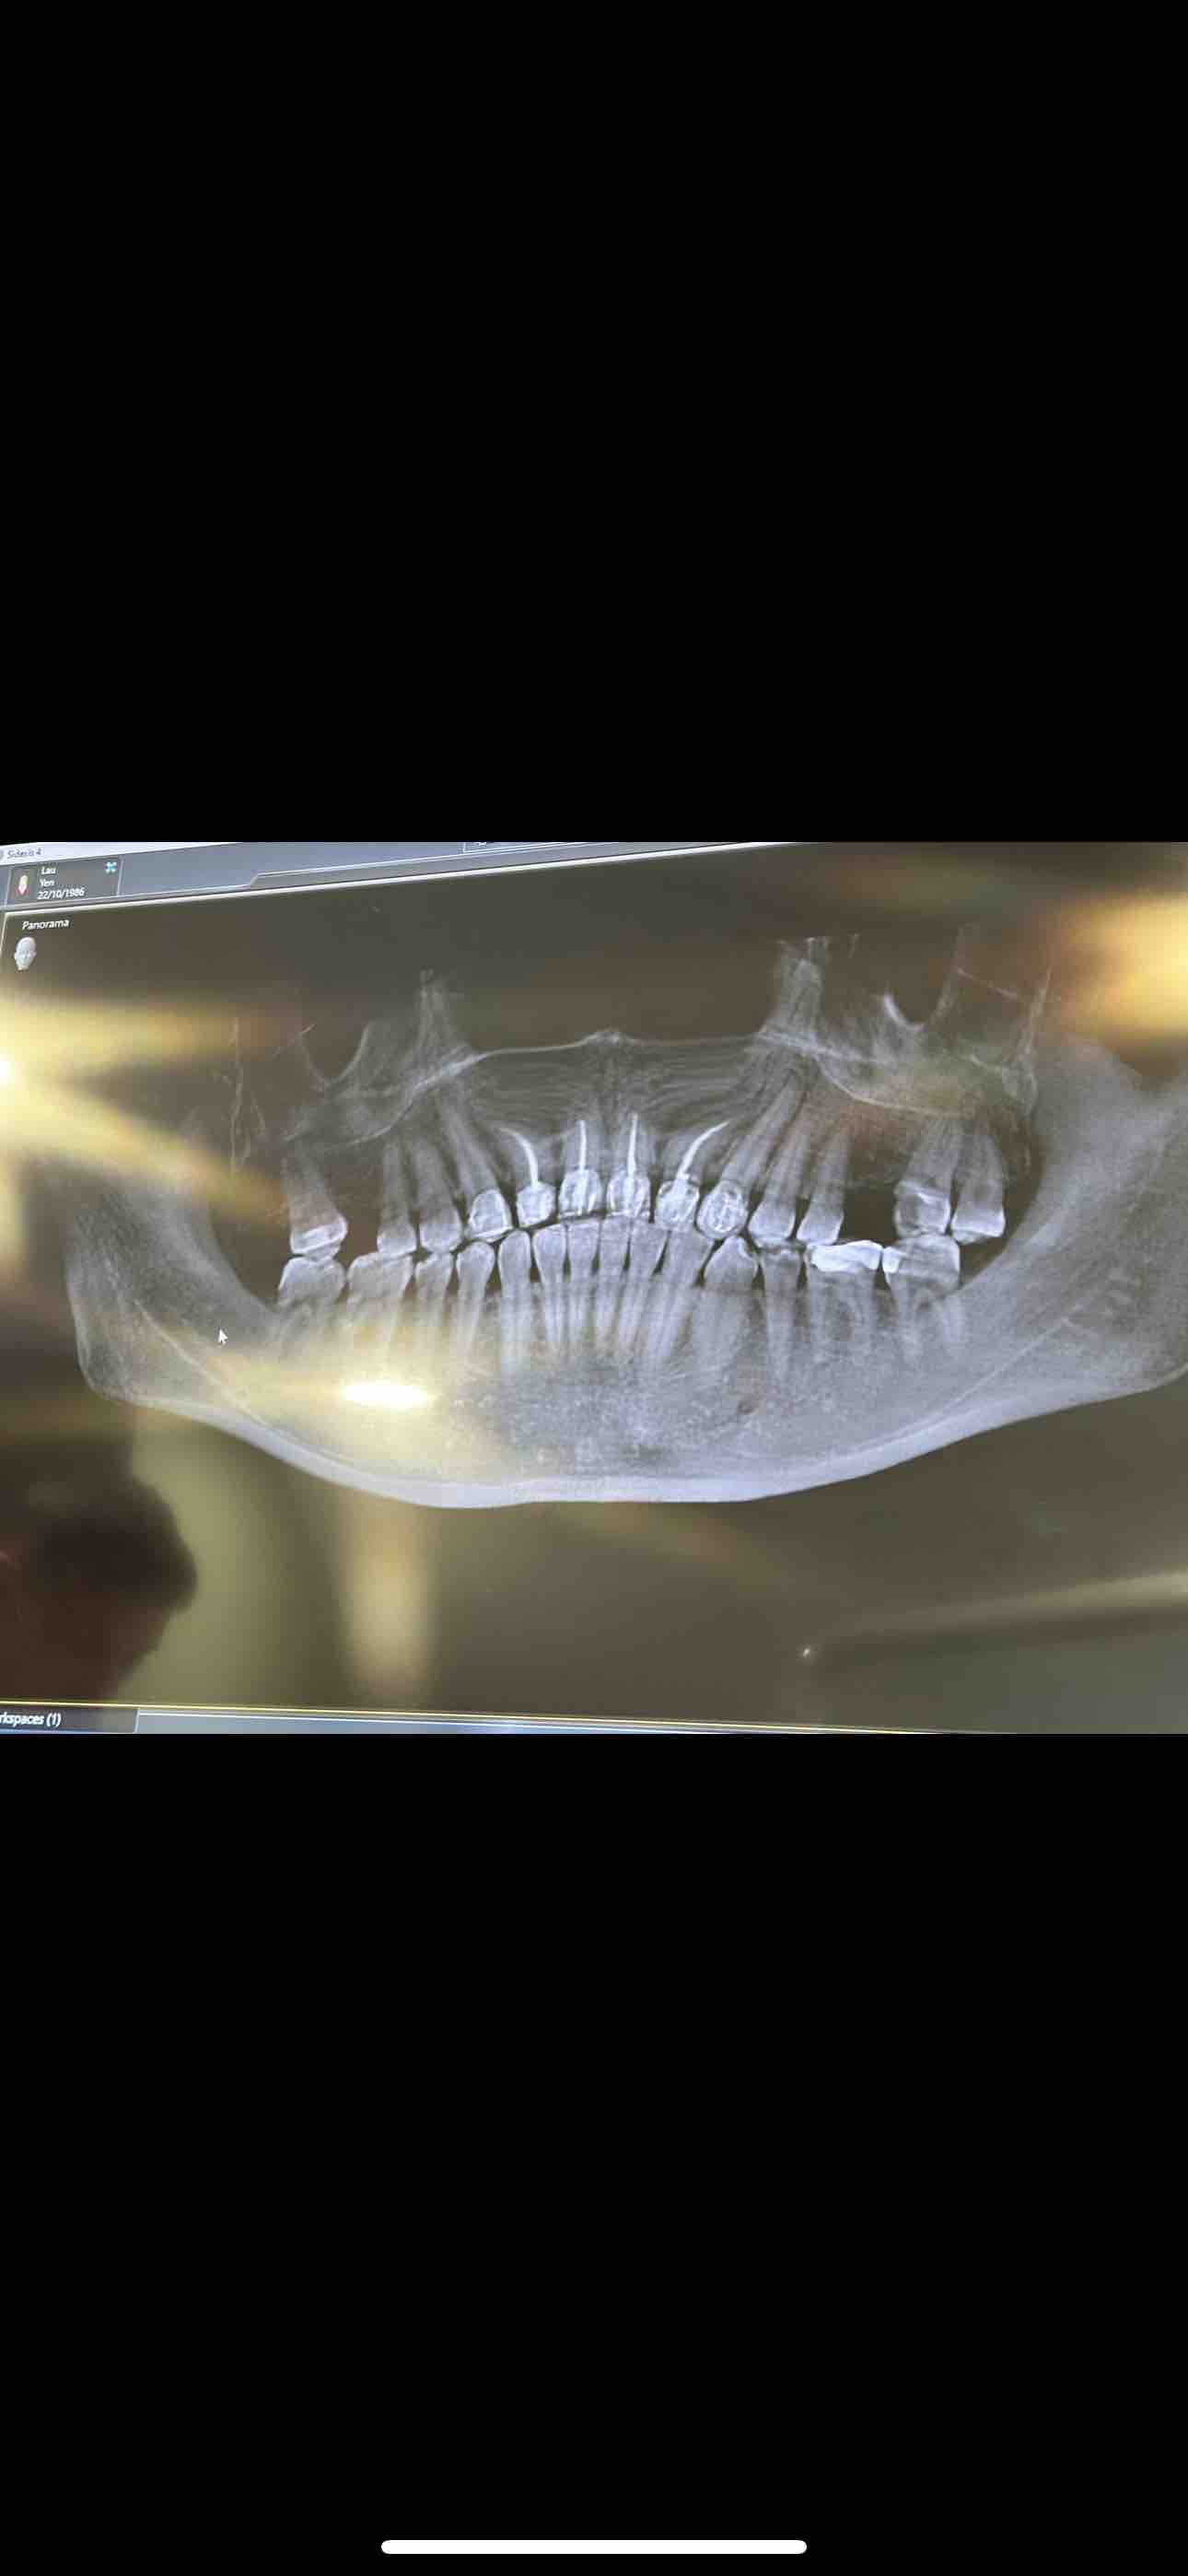

Since my treatments in Mexico I have since found the possibility’s of why my health hasn’t reached remission. I’m told my 4 upper root canals teeth are harbouring pathogens and bacteria becoming a breeding ground for Lyme to grow, that they are dead neurotic teeth , suppressing my immune system. I have done a dna connexions test to verify , which the results were shocking with over 18 gram bacteria residing in these teeth.

I had a meeting with a U.K. biological dentist in June 2024 and have had a cbct scan and vitally testing which can show which teeth are alive or dead. The scan showed that there could be 7 teeth to be removed and cavitation surgery required on previous extraction, due to the periodontal ligament was left inside which can cause bone infection.